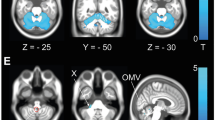

The GM and WM atrophy patterns were described in Fig. 2, Supplementary Figs. 7–13; statistical peaks in Table 2 for GM and Table 3 for WM; clusters gyral description in Supplementary Table 3 for GM and fascicle involvement in Supplementary Table 4 for WM. DARTEL and SUIT gives a similar atrophy description with the whole Cerebellum, cerebellar peduncles and Brainstem involved (Supplementary Tables 3, 4).

VBM comparison between controls and SCA2 patients. Upper left SCA2 versus controls GM comparison for DARTEL normalised data, SPM maps projected onto a 3D render of the template created by DARTEL, upper right SCA2 versus controls GM comparison for SUIT normalised data, SPM maps projected onto a 3D render of the SUIT template, lower left SCA2 versus controls WM comparison for SUIT normalised data, SPM maps projected onto 3 orthogonal planes of the SUIT template, blue cross on the global maxima, lower right SCA2 versus controls WM comparison for DARTEL normalised data, projected onto 3 orthogonal planes of the Colin27 template, blue cross on the global maxima, detail of the Corticospinal Tracts involvement. For all the contrasts, the threshold was p < 0.001 uncorrected

The pattern included: Lobules III–VI, Crus I–II, VIIb, VIII–X, Vermis I–X, Inferior/Middle/Superior Cerebellar Peduncles, Medulla, Midbrain, Pons, Medial Lemniscus and Pontine Crossing Tract. The atrophy extended with a number of voxels over the threshold of nearly 50% in the left and 50% in the right hemisphere (for both DARTEL and SUIT, see Supplementary Table 3). The atrophy extended slightly more in the Anterior Cerebellum compared to the Posterior (for both DARTEL and SUIT, see Supplementary Table 3). The maximum GM peaks differed for DARTEL and SUIT, where the order from max to min was Brainstem, Bilateral Posterior Cerebellum and Right Anterior Cerebellum for DARTEL (Table 2, Supplementary Table 3) and Brainstem, Right Anterior Cerebellum, and Bilateral Posterior Cerebellum for SUIT (Table 2, Supplementary Table 3). Both methods gave the same peak for WM: Right Middle Cerebellar Peduncles (Table 3).

Diffeomorphic Anatomical Registration Through Exponentiated Lie Algebra showed more extended clusters of atrophy, especially in Posterior Cerebellum, but also more voxels outside the GM atlas mask (Supplementary Table 3).

Additionally only DARTEL can show significant voxels outside Cerebellum and, indeed, there were several: in the Left Inferior Parietal Lobule (see Table 2 and Supplementary Fig. 12) and along the Cortico Spinal Tracts (they agreeably followed the a priori known shape of the fascicle, see Table 3; Fig. 2, lower right and Supplementary Fig. 13).

We did not find any significant correlation with SPM8 for ICARS, CAG repeats and duration of the disease. We found a striking correlation with the two version of ToL (Fig. 3, Supplementary Fig. 14, 15, 16; Table 4, Supplementary Table 6). The ToL PEG correlated with a prevalently (83%) Anterior Cerebellum area of about 20,000 voxels with global maxima in x, y, z = 31, −33, −27 (Right Lobule IV–V near the boundary with Lobule VI). The clusters extended more in the Right Cerebellum (68%) and included many voxels in Lobules III–VI with small parts of the Right Parahippocampal Gyrus, Crus 1, 2 and Midbrain (Supplementary Table 6). The ToL CPU correlated with areas prevalently centred on the Posterior Cerebellum (71%) of about 25,000 voxels with global maxima in x, y, z = 38, −76, −36 (Right Crus 1 near the boundary with Crus 2). The clusters extended more in the Right Cerebellum (78%) and included Lobules III–VI, Crus 1, 2, VIII, Vermis I–V, Right Hippocampus and Parahippocampal Gyrus with small parts of Midbrain, Left Hippocampus and Parahippocampal Gyrus (Supplementary Table 6).

Correlation between Tower of London scores and atrophy patterns. Upper left Traditional Tower of London scores (ToL PEG) for controls (in blue, left histogram) and SCA2 (in green, right histogram), upper right Computerised Tower of London scores (ToL CPU) for controls (in blue, left histogram) and SCA2 (in green, right histogram). Error bars stand for SEM, *p < 0.05 two independent samples t test, ordinates units are in percent of maximum score. Lower left voxels volume correlated with ToL PEG, blue cross on the global maxima x, y, z = 31, −33, −27 mm; Lower right voxels volume correlated with ToL CPU, blue cross on the global maxima x, y, z = 38, −76, −36 mm. For all the contrasts the threshold was p < 0.001 uncorrected